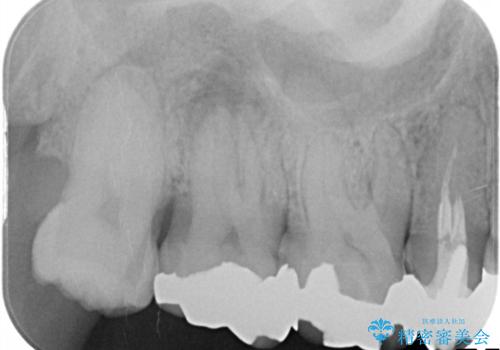

精密な診査の結果、一番奥の7番目の歯の根の先に、根尖病変(膿の袋)が認められました。そのため、単に被せ物を新しくするだけでなく、まずは土台となる根の状態を整える必要があると判断。右上7番には再発を防ぐための精密根管治療を行い、その後、5番・6番・7番の3本全てを、強度と審美性に優れたセラミッククラウンで修復する計画を立案しました。

精密根管治療 右上7番に対して、歯科用顕微鏡などを用いた精密根管治療を実施しました。根管内の感染源を徹底的に除去し、緊密に充填。経過観察の結果、根尖病変は完全に消失し、健康な状態を取り戻すことができました。